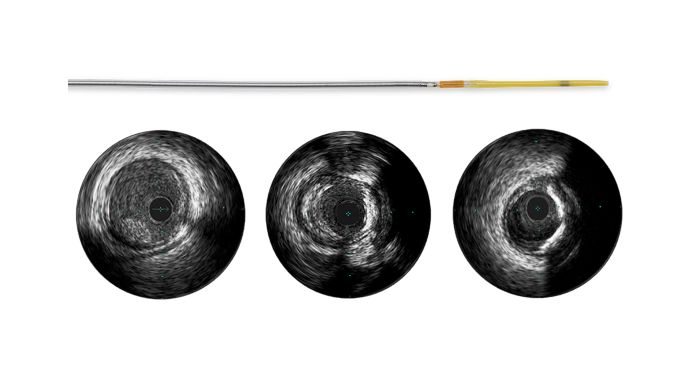

Coronary IVUS

Visualize the best path forward with IVUS

Intravascular ultrasound allows physicians to visualize blood vessels from the inside out. Cross-sectional images help assess presence and extent of disease, plaque geometry and morphology, guide wire position during lesion crossing, and stent position post-treatment. The imaging transducer emits high-frequency sound waves that echo off vessel walls and are sent back to the system in varying intensities depending on the tissue. System electronics process the signal to display the cross-sectional image.